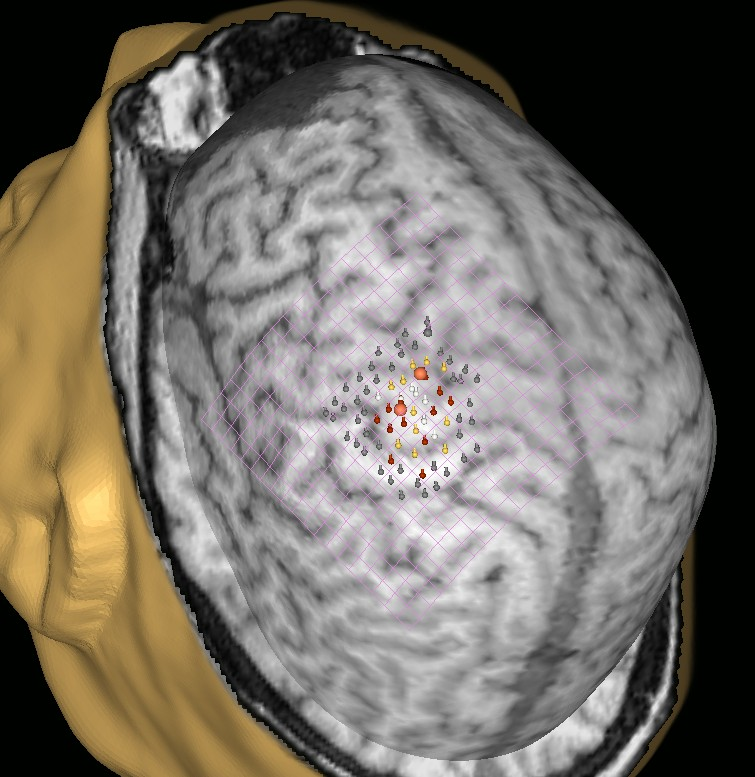

In our practice we use patented method7 of CMD detection based on navigated brain stimulation which is called NBS-CMD-test. The principle of method is following: first step is mapping of individual localization of motor cortical zones via NBS, in our protocol it was zone responsible for musculus abductor pollicis movements (Figure 1). Secondly this motor zone was stimulated with magnetic stumuli: 10 of them were provided without any facilitation and next 10 were accompanied with an audial command, ordering patient to raise his hand. Then all the amplitudes of received motor responses, registered with myographic tracking, were averaged out. In case averaged amplitude of facilitated stimuli exceeds non-facilitated amplitude by more than 20%, the result of NBS-CMD-test was ranked as a positive. That meaned, that clinically unresponsive patient heard an audial command, understood it and tried to execute it, but failed due to neurological deficit. Thus, we concluded that positive result of NBS-CMD-test indicates the presence of CMD in such a patient.

Figure 1 Upper extremity motor cortical representation.

Evoked motor responses with >1000 mkV amplitude are marked with white dots; 500-1000 mkV – yellow dots, 50-500 mkV – red dots; <50 mkV or without myographic response – grey dots.